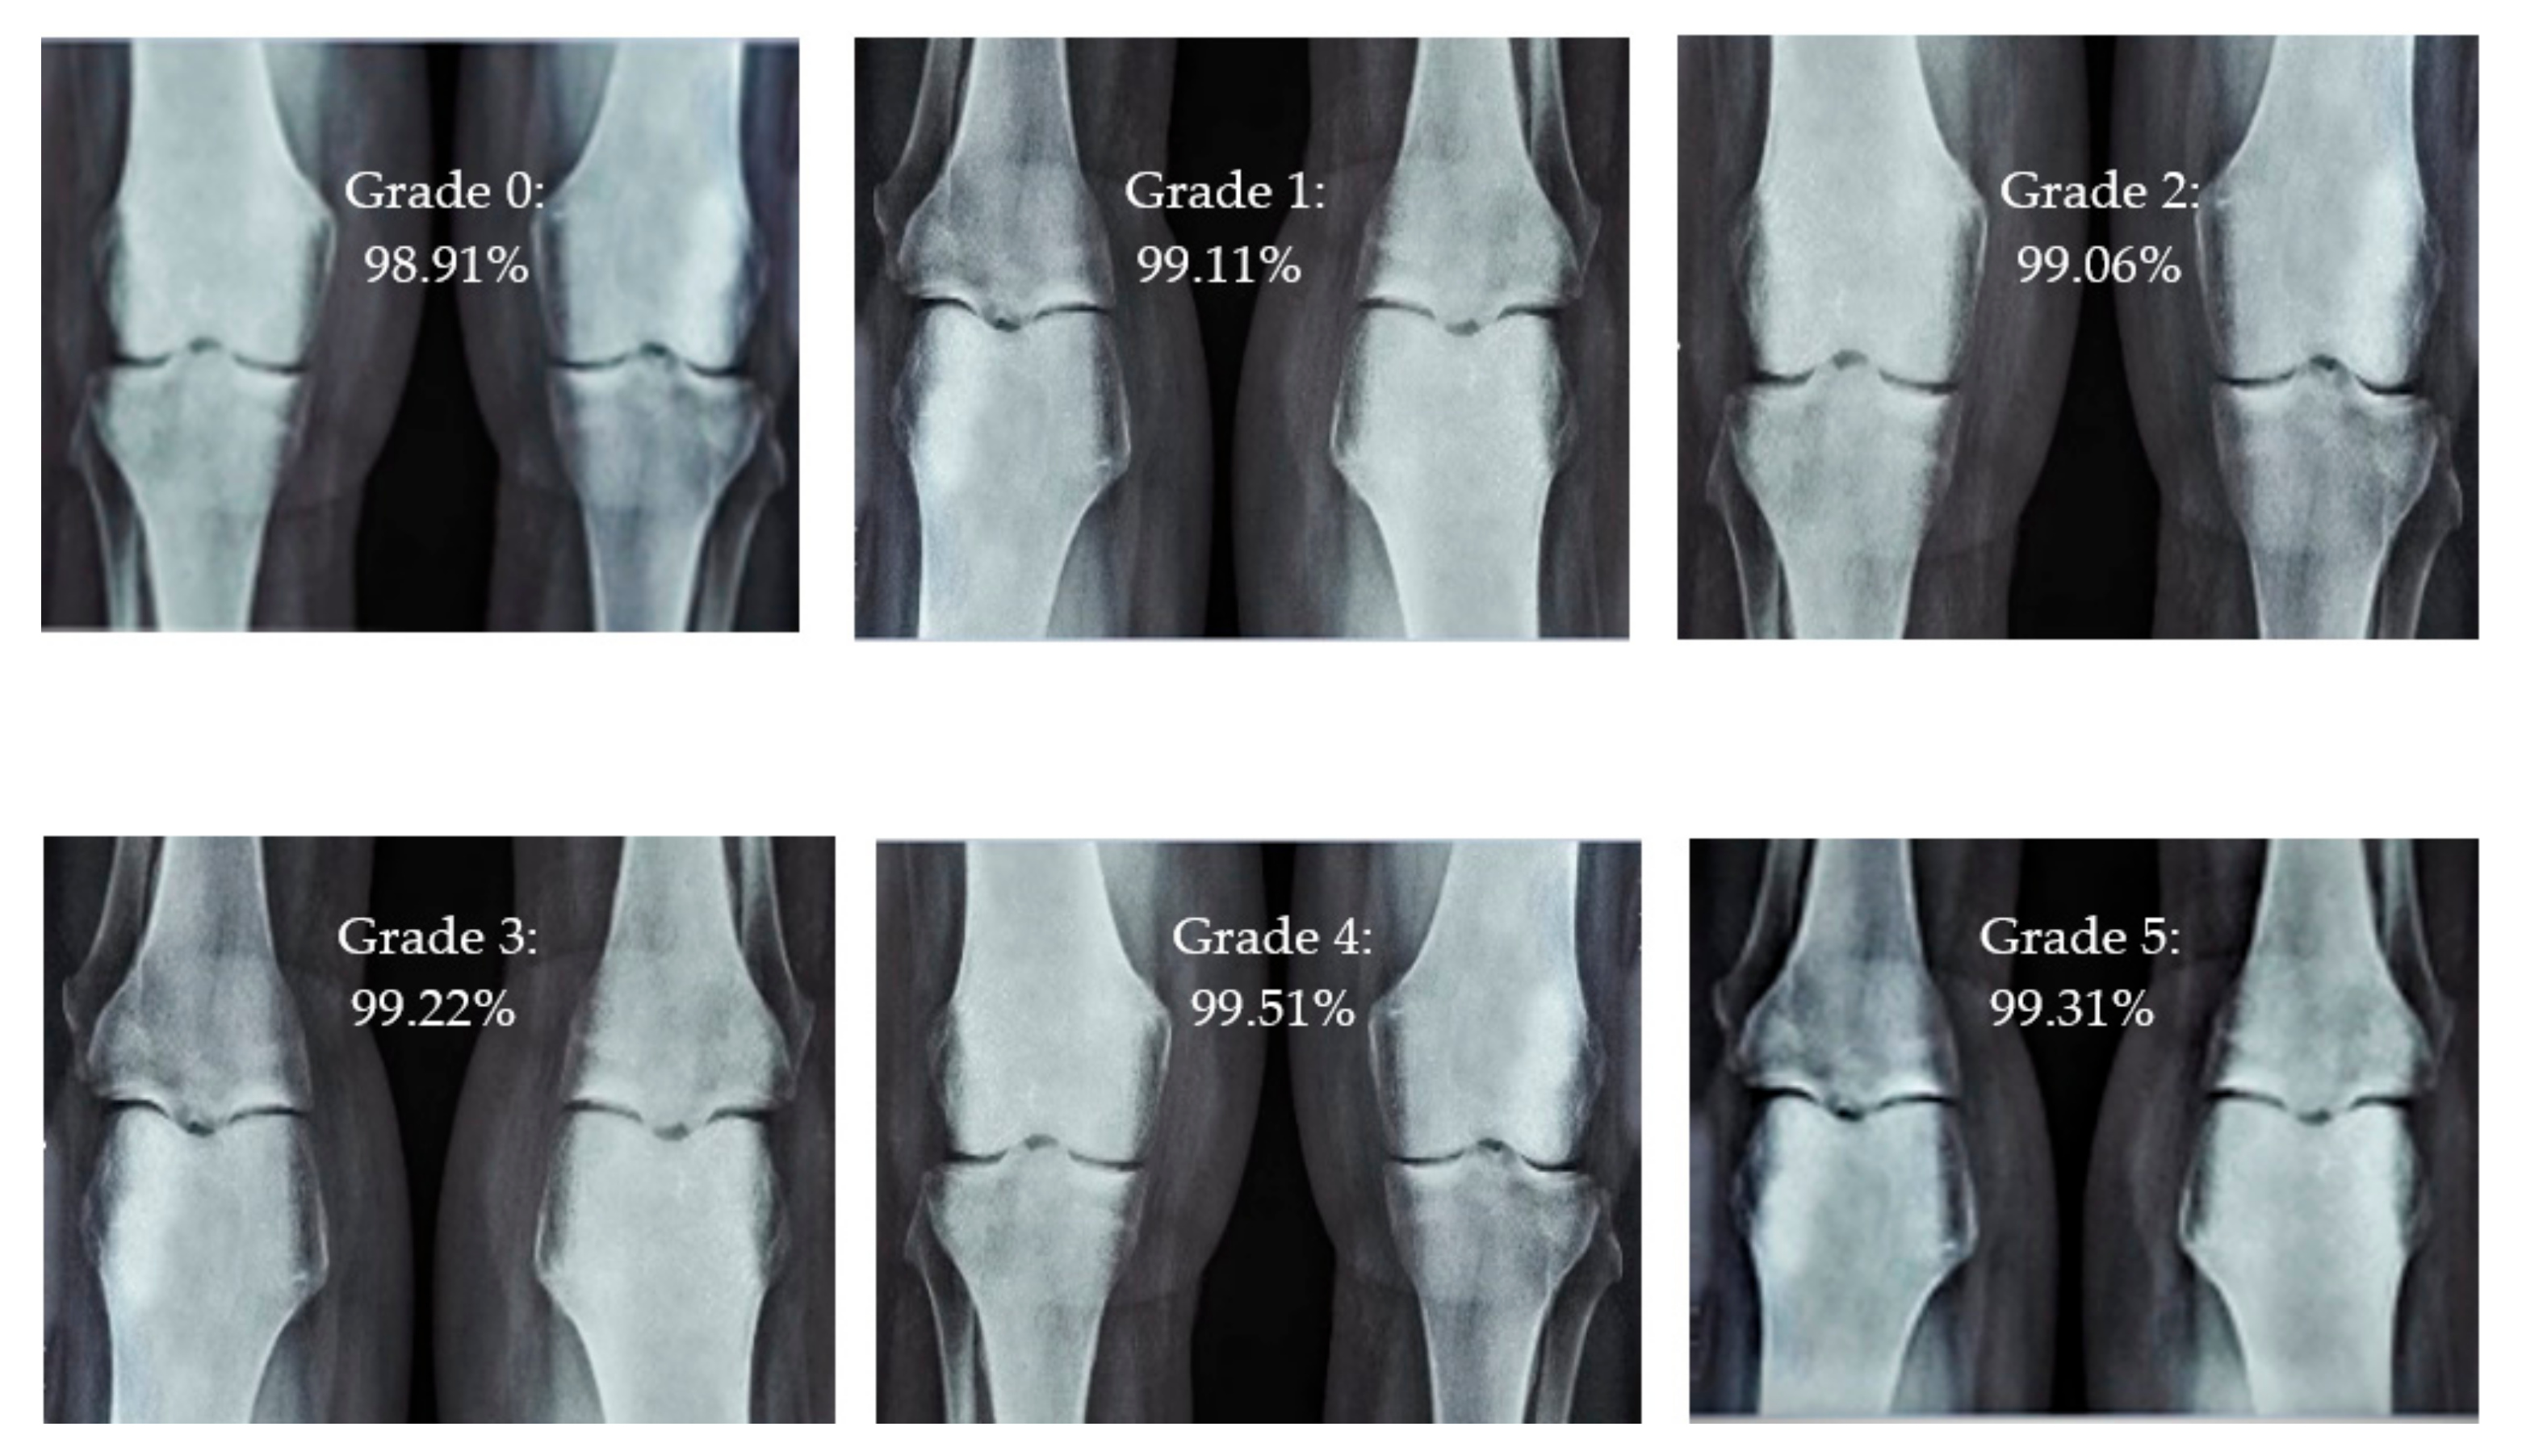

For knee RA severity classification, we conducted this research using a modified version of the VGG16 architecture and a domain adaptation technique, as shown in Figure 3. The VGG16 model was made up of five convolutional layers, three max-pooling layers, and three fully connected layers—all the digital X-radiation images needed to be resized to (227 × 227 × 3). In our implementation, X-radiation image information for training purposes accounted for eighty percent of the total, while X-radiation image information for evaluating purposes accounted for twenty percent. Although there are sixteen layers in VGG16, only a subset of those layers is required for feature extraction. In order to shorten the amount of time needed for training and establish more control over the fitting process, we assigned a dropout ratio value of 0.5 to the completely connected layer (fcl6) and the fully connected layer (fcl7). The characteristics were taken from the fully connected layers designated fcl6 and fcl7, respectively. To categorize the retrieved features into 1000 categories, VGG16’s architecture used a fully connected layer (fcl8). Then, we conducted one last round of tuning on the pre-trained VGG16 model’s ability to classify RA by changing parameters in the model’s last three layers. The model’s last three layers were swapped out for a fully linked layer, a softmax layer, and a classification layer. In addition, a newly linked layer was assigned to five groups of RA grades for the dataset: Grade 0, Grade 1, Grade 2, Grade 3, and Grade 4. We trained the proposed network by using digital knee X-radiations, a small-batch test dataset, gradient descent, and maximal epochs. Our proposed network learning strategy used stochastic gradient descent, and we compared its performance to previous efforts. The proportion of knee X-radiation images from the test set for which the network correctly predicted the RA grade was used to calculate proposed work accuracy. The proposed approach achieved an overall accuracy of 99.10% in classifying knee RA cases. Table 5 illustrates the Visual Geometry Group (VGG16) CNN operation for RA grade classification. Figure 4, depicts the RA classification using VGG16 architecture.

3.4. Intensity Classification of Rheumatoid Arthritis

The presented model achieved 99.10% accuracy on the whole test set. The confusion matrix of the presented method is shown in Figure 8, and its performance is compared in detail to that of current methods in Table 5. In Figure 8, we examine the training and learning procedure as a whole to assess the planned activity’s success. Table 6 demonstrates the highest accuracy rate for classifying CBD grades zero–three–four knee joints. The knee joints with a CBD grade of one or two are the toughest to categorize. As can be seen in Figure 8, there is only a marginal amount of room for error when classifying knee joints as CBD Grades zero, three, or four. Knee joints that are classified as CBD Grades one or two have a small number of marginal misclassifications. In several circumstances, the proposed approach incorrectly estimated CBD Grade two as Grade one and vice versa. Joint space narrowing and bony spur development are significantly different in CBD Grade four knee joints. However, CBD-grade one knee joints show little change in JSN or osteophyte growth compared with the other classes. Types of knee RA and their intensity levels are shown in Figure 5. Table 8 and Figure 9 illustrate the JSN accuracy of the proposed and other state-of-the-art methods comparison.

Figure 5. Different CBD grade levels of knee rheumatoid arthritis.